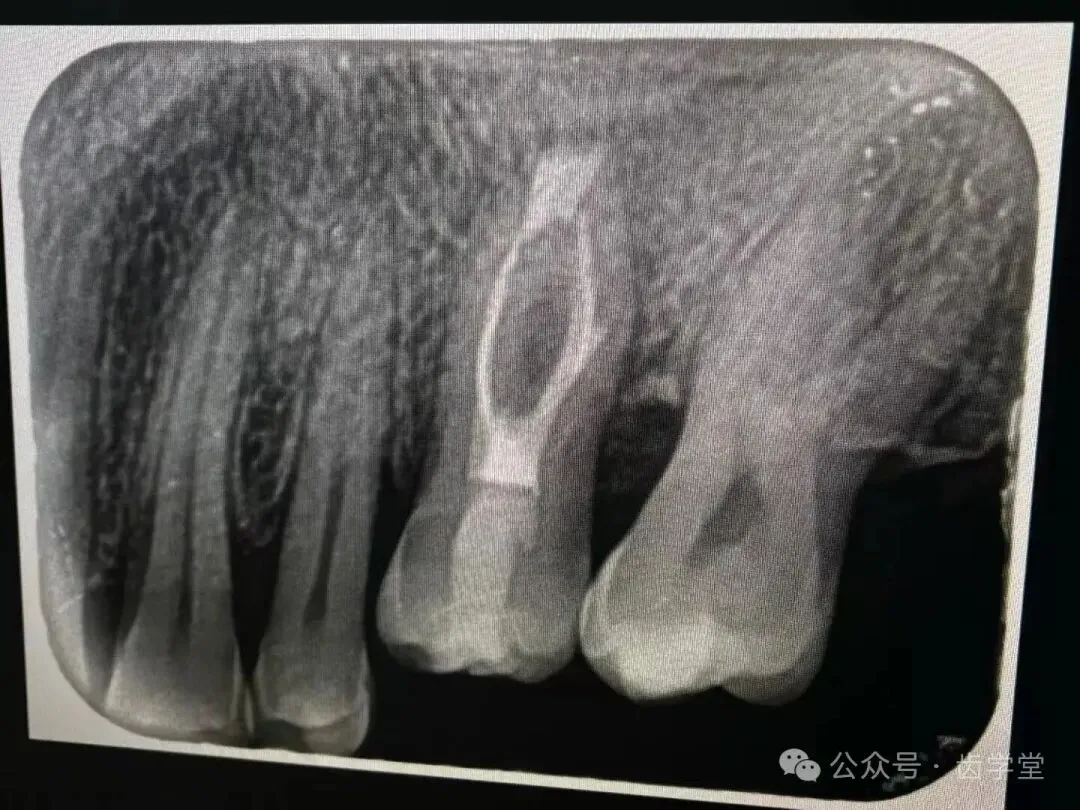

8. 自体牙移植的术前检查、评估和准备;

11.3D供牙模型的打印及使用技巧;

13.受植位点不同情况移植的区别及其要点;

26.上颌后牙窦嵴距不足时处理方法;

27.下颌后牙管嵴距不足时处理方法;